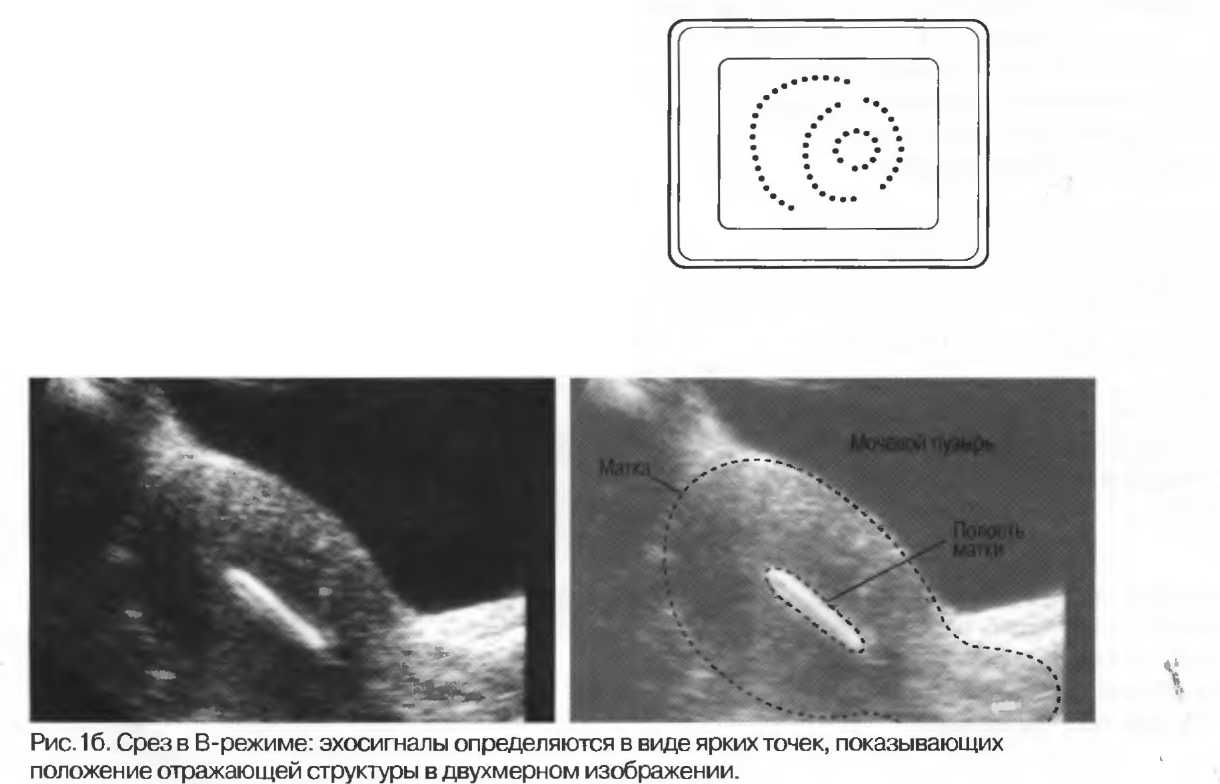

2. В-режим. В этом режиме все ткани, через которые проходит ультразвуковой луч, получают отображение на экране. Получаемые двухмерные изображения называются изображениями в В-режиме или срезами в В-режиме (рис. 16). При быстром чередовании В-срезом получается видеомониторное наблюдение.